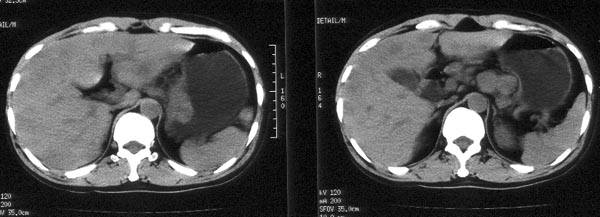

男性,46岁。腹痛月余。胃镜检查示“胃贲门区占位”,活检病理示

“胃贲门癌”。

ct平扫:胃贲门部见软组织肿物突入胃腔内,大小4x3cm,浅分叶状,中央密度较低,邻近胃壁增厚。外缘与周围组织分界清。im25层面,小网膜囊区见两枚肿大淋巴结,直径均约3cm。肝脏大小正常,肝内散在分布多个大小不等的类圆形低密度影,最大者位于肝右前叶上段,直径约4cm,病灶边缘模糊,与正常肝实质分界欠清。

ct诊断:胃贲门癌,并腹腔淋巴结转移及肝内多发转移。